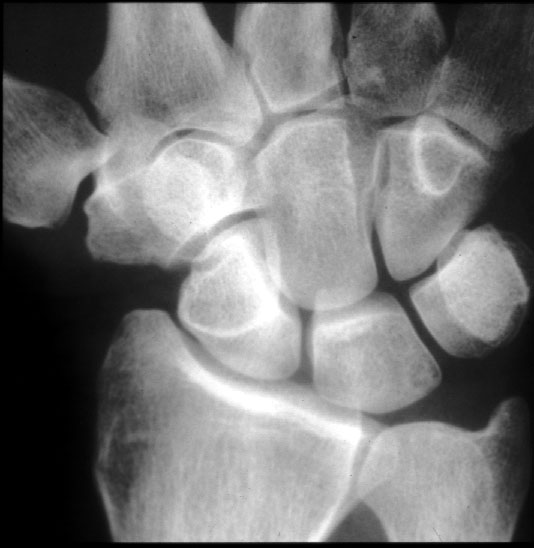

Normal Wrist (frontal) -- Identify: radial styloid, ulnar styloid, navicular

(scaphoid), lunate, triquitrum, pisiform, trapezium, trapezoid, capitate,

hamate, all metacarpals